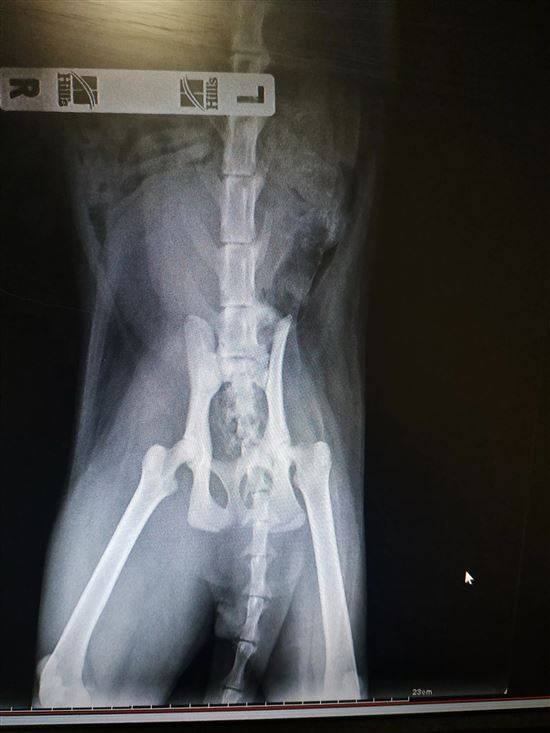

Пожилая кошка с дисплазией тазобедренного сустава

Белыми стрелками обозначено большое количество стула в толстой кишке указанной кошки с дисплазией тазобедренного сустава. Этой кошке больно сидеть на корточках, чтобы опорожнить кишечник, в результате чего у нее сильно запор.

Другие болезни, вызывающие хромоту или болезненность задних ног, могут имитировать дисплазию тазобедренного сустава.